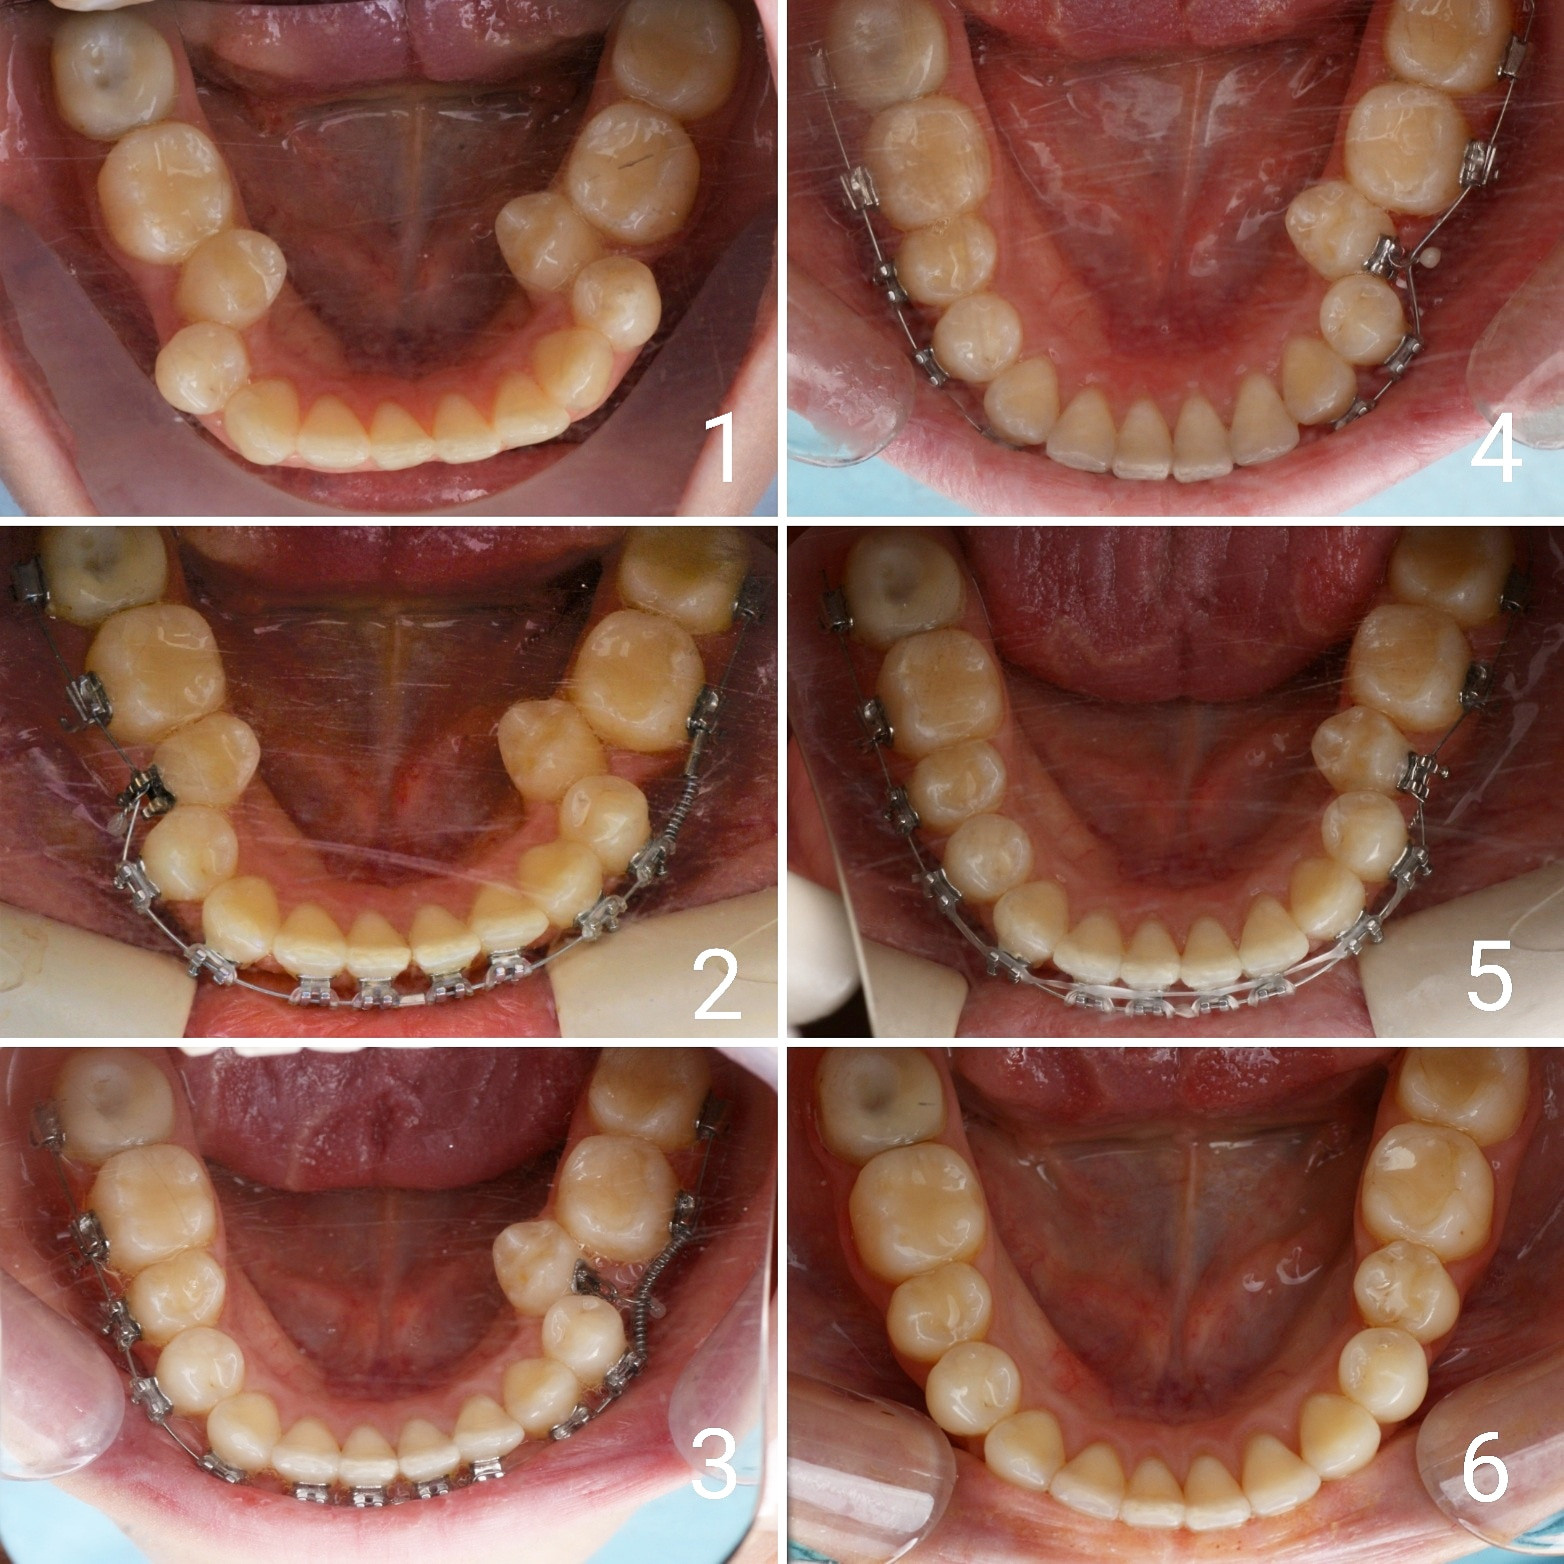

Большое путешествие зубов на своё законное место.

Эта фраза знакома многим ответственным родителям, которые привели на приём к ОРТОДОНТУ своего ребёнка в 5-10 лет, заподозрив проблему или понимая, что места постоянным зубам откровенно не хватает! Горькая правда в том, что брекеты - не волшебное средство от всех проблем, они "расставляют" зубы внутри сформированого объёма челюсти, но никак не влияют на её рост. Родители ждут, а тем временем драгоценное время, когда ребёнок растёт, уходит... Во взрослом возрасте приходится удалять здоровые зубы или прибегать к ортогнатической хирургической операции. 📸 На фото узкая нижняя челюсть, места постоянным зубам нет, боковые резцы прорезываются "вторым рядом".

✅ Помогаем с помощью расширяющей дуги, пружины и зацепных элементов, которые зафиксированы на МОЛОЧНЫЕ зубы